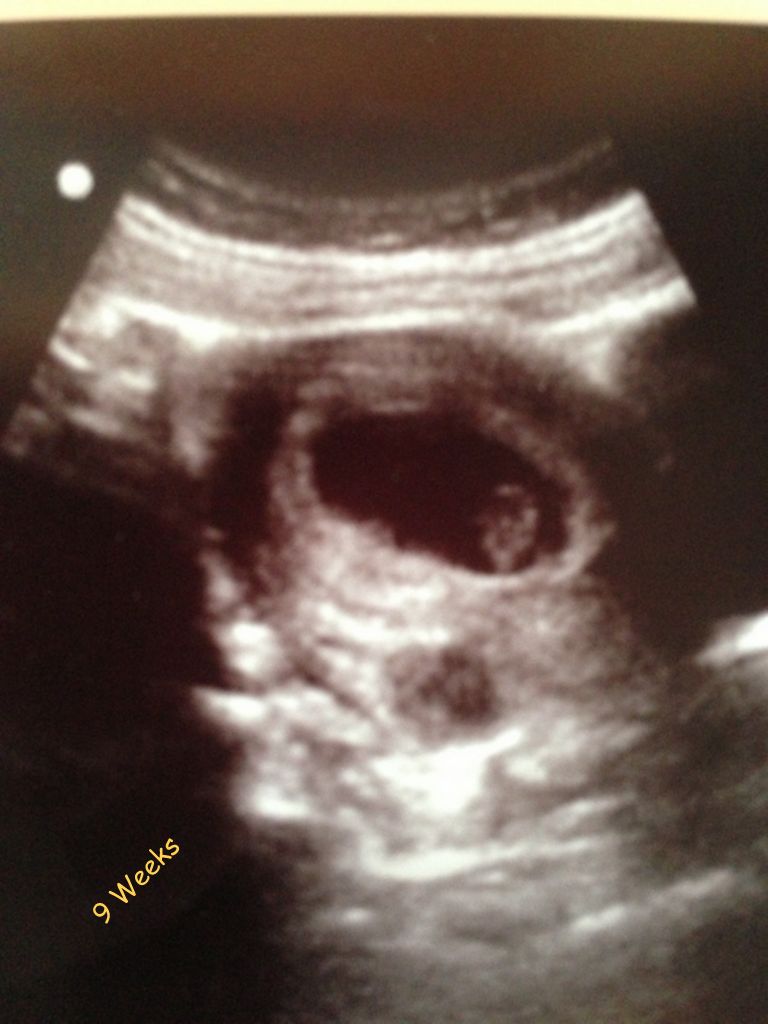

06.11.2014 - Grishka's First Days -- img_0228.jpg